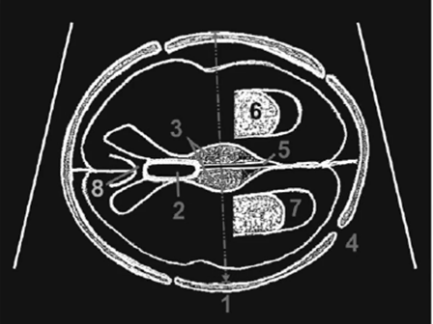

The proposed methodology follows a segmentation-driven deep learning pipeline for fetal head parameter extraction and abnormality detection from ultrasound images.

1.Data Acquisition

Ultrasound images of the fetal head are collected from publicly available datasets (such as HC18) or clinical sources. The dataset includes labeled images containing fetal head boundaries and corresponding biometric measurements.

3.Fetal Head Segmentation

A deep learning model, typically U-Net or an enhanced variant (Attention U-Net / Residual U-Net), is trained to segment the fetal head region from ultrasound images. The model learns pixel-level features to accurately distinguish the head boundary from the background.

4.Head Parameter Extraction

After segmentation, geometric methods are applied to extract fetal head parameters:

- Head Circumference (HC)

- Biparietal Diameter (BPD)